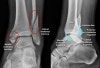

X-ray : 양과 골절(Bimalleolar fracture)

불안정골절 중 양과골절(bimalleolar fracture)은 안쪽, 바깥쪽 복사 모두 골절 혹은 비골 원위부 골절과 삼각인대 손상이 같이 있는 경우입니다.